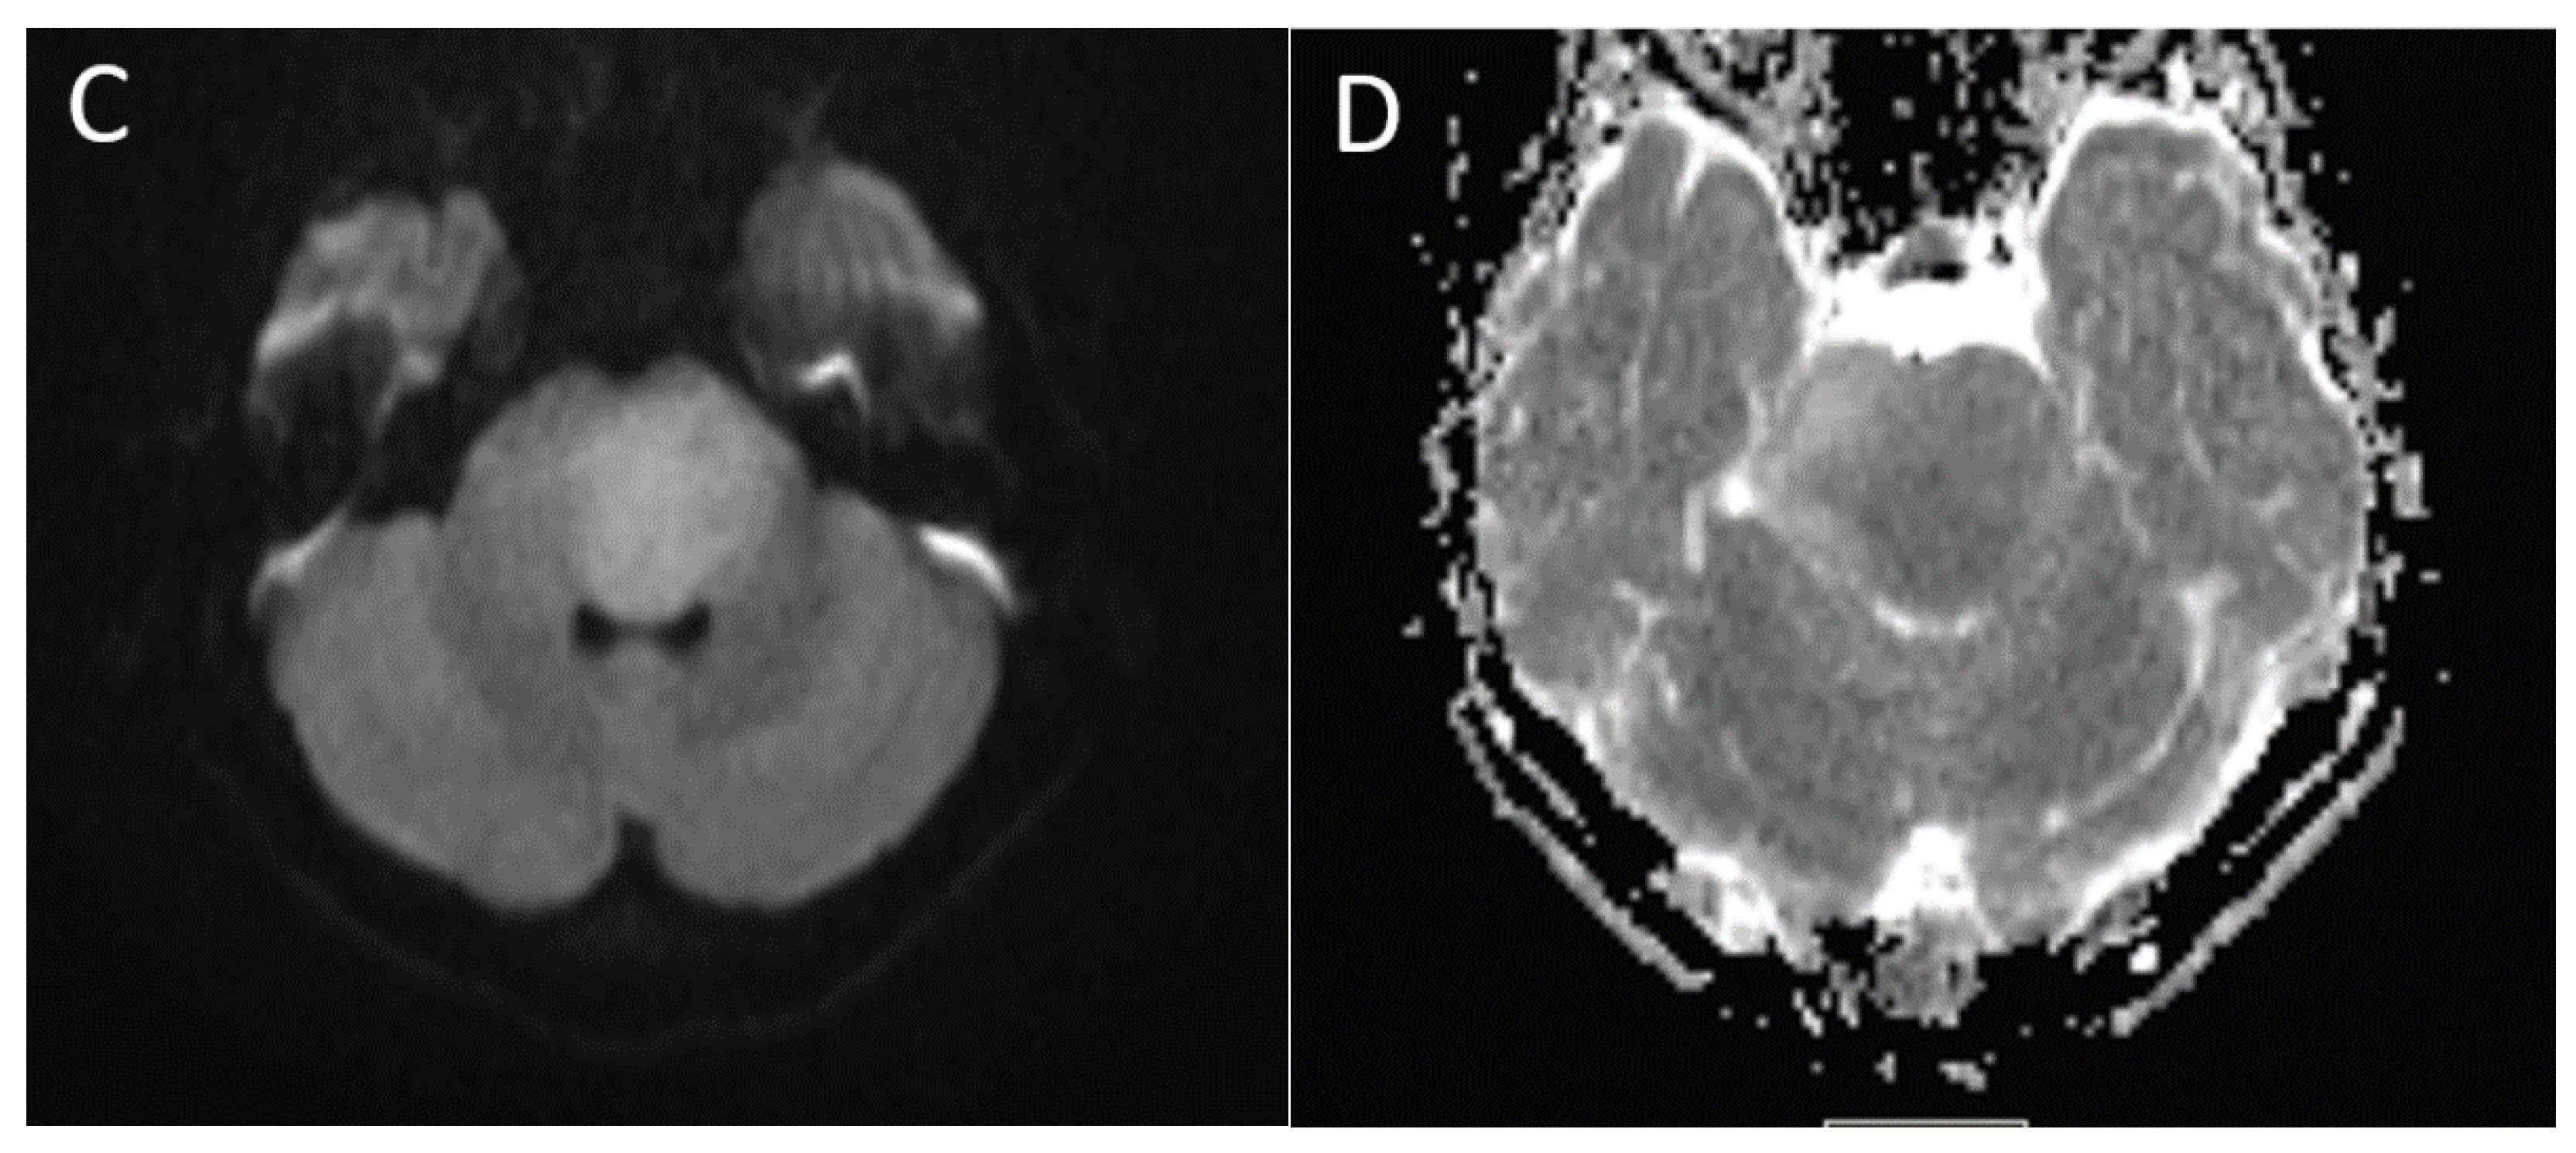

| Medulloblastoma | Exclusively posterior fossa Most commonly in fourth ventricle/cerebellar vermis (non-WNT, non-SHH, or WNT), can involve cerebellopontine angle (WNT) or cerebellar hemispheres with extra-axial extension (SHH) | Diffusion restricting Variable enhancement Cystic/necrotic change may be present Calcifications uncommon Taurine peak characteristic |

| Posterior fossa ependymoma | Fourth ventricle (PFB) or cerebellopontine angle (PFA) | Heterogeneous mass Calcifications common Intermediate diffusion (between medulloblastoma and pilocytic astrocytoma) Usually enhancing High myo-inositol on MRS |